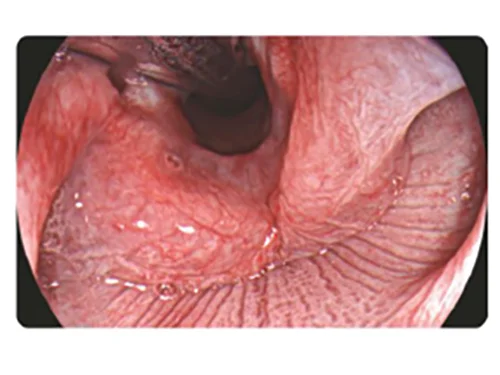

Видеоэндоскопическая система Concemed V-800

Профессиональный комплекс с видеопроцессором, 4-светодиодным источником света и Full HD визуализацией. Три оптических режима (TEI, DSI, PSI) для диагностики новообразований, воспалений и оценки глубины инфильтрации. Поддерживает горячую замену эндоскопов, оснащена памятью 1 ТБ, DICOM и 8-дюймовым сенсорным экраном.

Concemed V-800 — это экспертная видеоэндоскопическая система, сочетающая высокое качество визуализации, специальные оптические режимы и удобство использования. В состав системы входят: видеопроцессор, видеогастроскоп, видеоколоноскоп, медицинский монитор и эндоскопическая тележка.

Основные характеристики видеоэндоскопической системы V-800:

- Интегрированный источник света с 4 светодиодами, срок службы 20 000 часов

- Функция смены эндоскопа без выключения системы (горячая замена)

- Объем встроенной памяти — 1 Тб

- Многомодовая лазерная передача, высокая скорость и устойчивость передачи сигнала

- DICOM передача данных

- Емкость для воды сочетает функции встроенного воздушного насоса и насоса для CO2

- Широкий угол обзора эндоскопов: 145° у видеогастроскопа, 170° у видеоколоноскопа

- Высококачественное изображение Full HD с высокой четкостью и минимальными искажениями

- Три специальных световых режима

8-дюймовый сенсорный экран с возможностью персонализированной настройки

Специальные оптические режимы:

Визуализация с улучшением текстуры и цвета (TEI)

Визуализация с улучшением текстуры и цвета (TEI)

Подчеркивает контуры и четкость структур, что позволяет улучшать видимость мелких и плоских образований.

Узкоспектральная дихроматическая визуализация (DSI)

Узкоспектральная дихроматическая визуализация (DSI)

Выявление и классификация опухолевых образований, прогнозирование глубины инфильтрации.

Полихроматическая спектральная визуализация (PSI)

Полихроматическая спектральная визуализация (PSI)

Упрощает выявление воспалительных изменений, образований в виде углублений и ниш.

DSI: Узкоспектральная двухцветная визуализацияа

Свет фиолетового и зеленого спектров наиболее эффективно поглощается гемоглобином, что снижает отражение и рассеяние и позволяет четко визуализировать поверхностные сосуды слизистой оболочки. Увеличивает контраст между кровеносными сосудами и окружающей тканью.

Применение

- Точное обследование пораженных участков слизистой.

- Определение инфильтрации и границы пораженного участка.

- Выявление и классификация опухолевых образований.

Белый свет

DSI

PSI: Спектральная визуализация цветовой палитры полихроматическая визуализация

Выравнивает пропорции узкополосного фиолетового и красного цвета на основе белого цвета и использование алгоритмов сложения для повышения цветового контраста.

Применение

- Повышение вероятности обнаружения поражений, таких как воспаление, атрофия, рак на ранних стадиях, полипы и иные поражения при среднем и слабом увеличении и повышение эффективности обследования.

Белый свет

PSI

TEI: Визуализация с улучшением текстуры и цвета

Улучшение текстуры и цвета наряду со сбалансированной однородностью яркости подчеркивает контуры структур, повышает четкость изображения, позволяет улучшать видимость мелких и плоских образований.

Применение

- Диагностика воспалений и плоских блюдцеобразных поражений

- Изучение морфологии слизистой оболочки для обнаружения поражений.

Белый свет

TEI